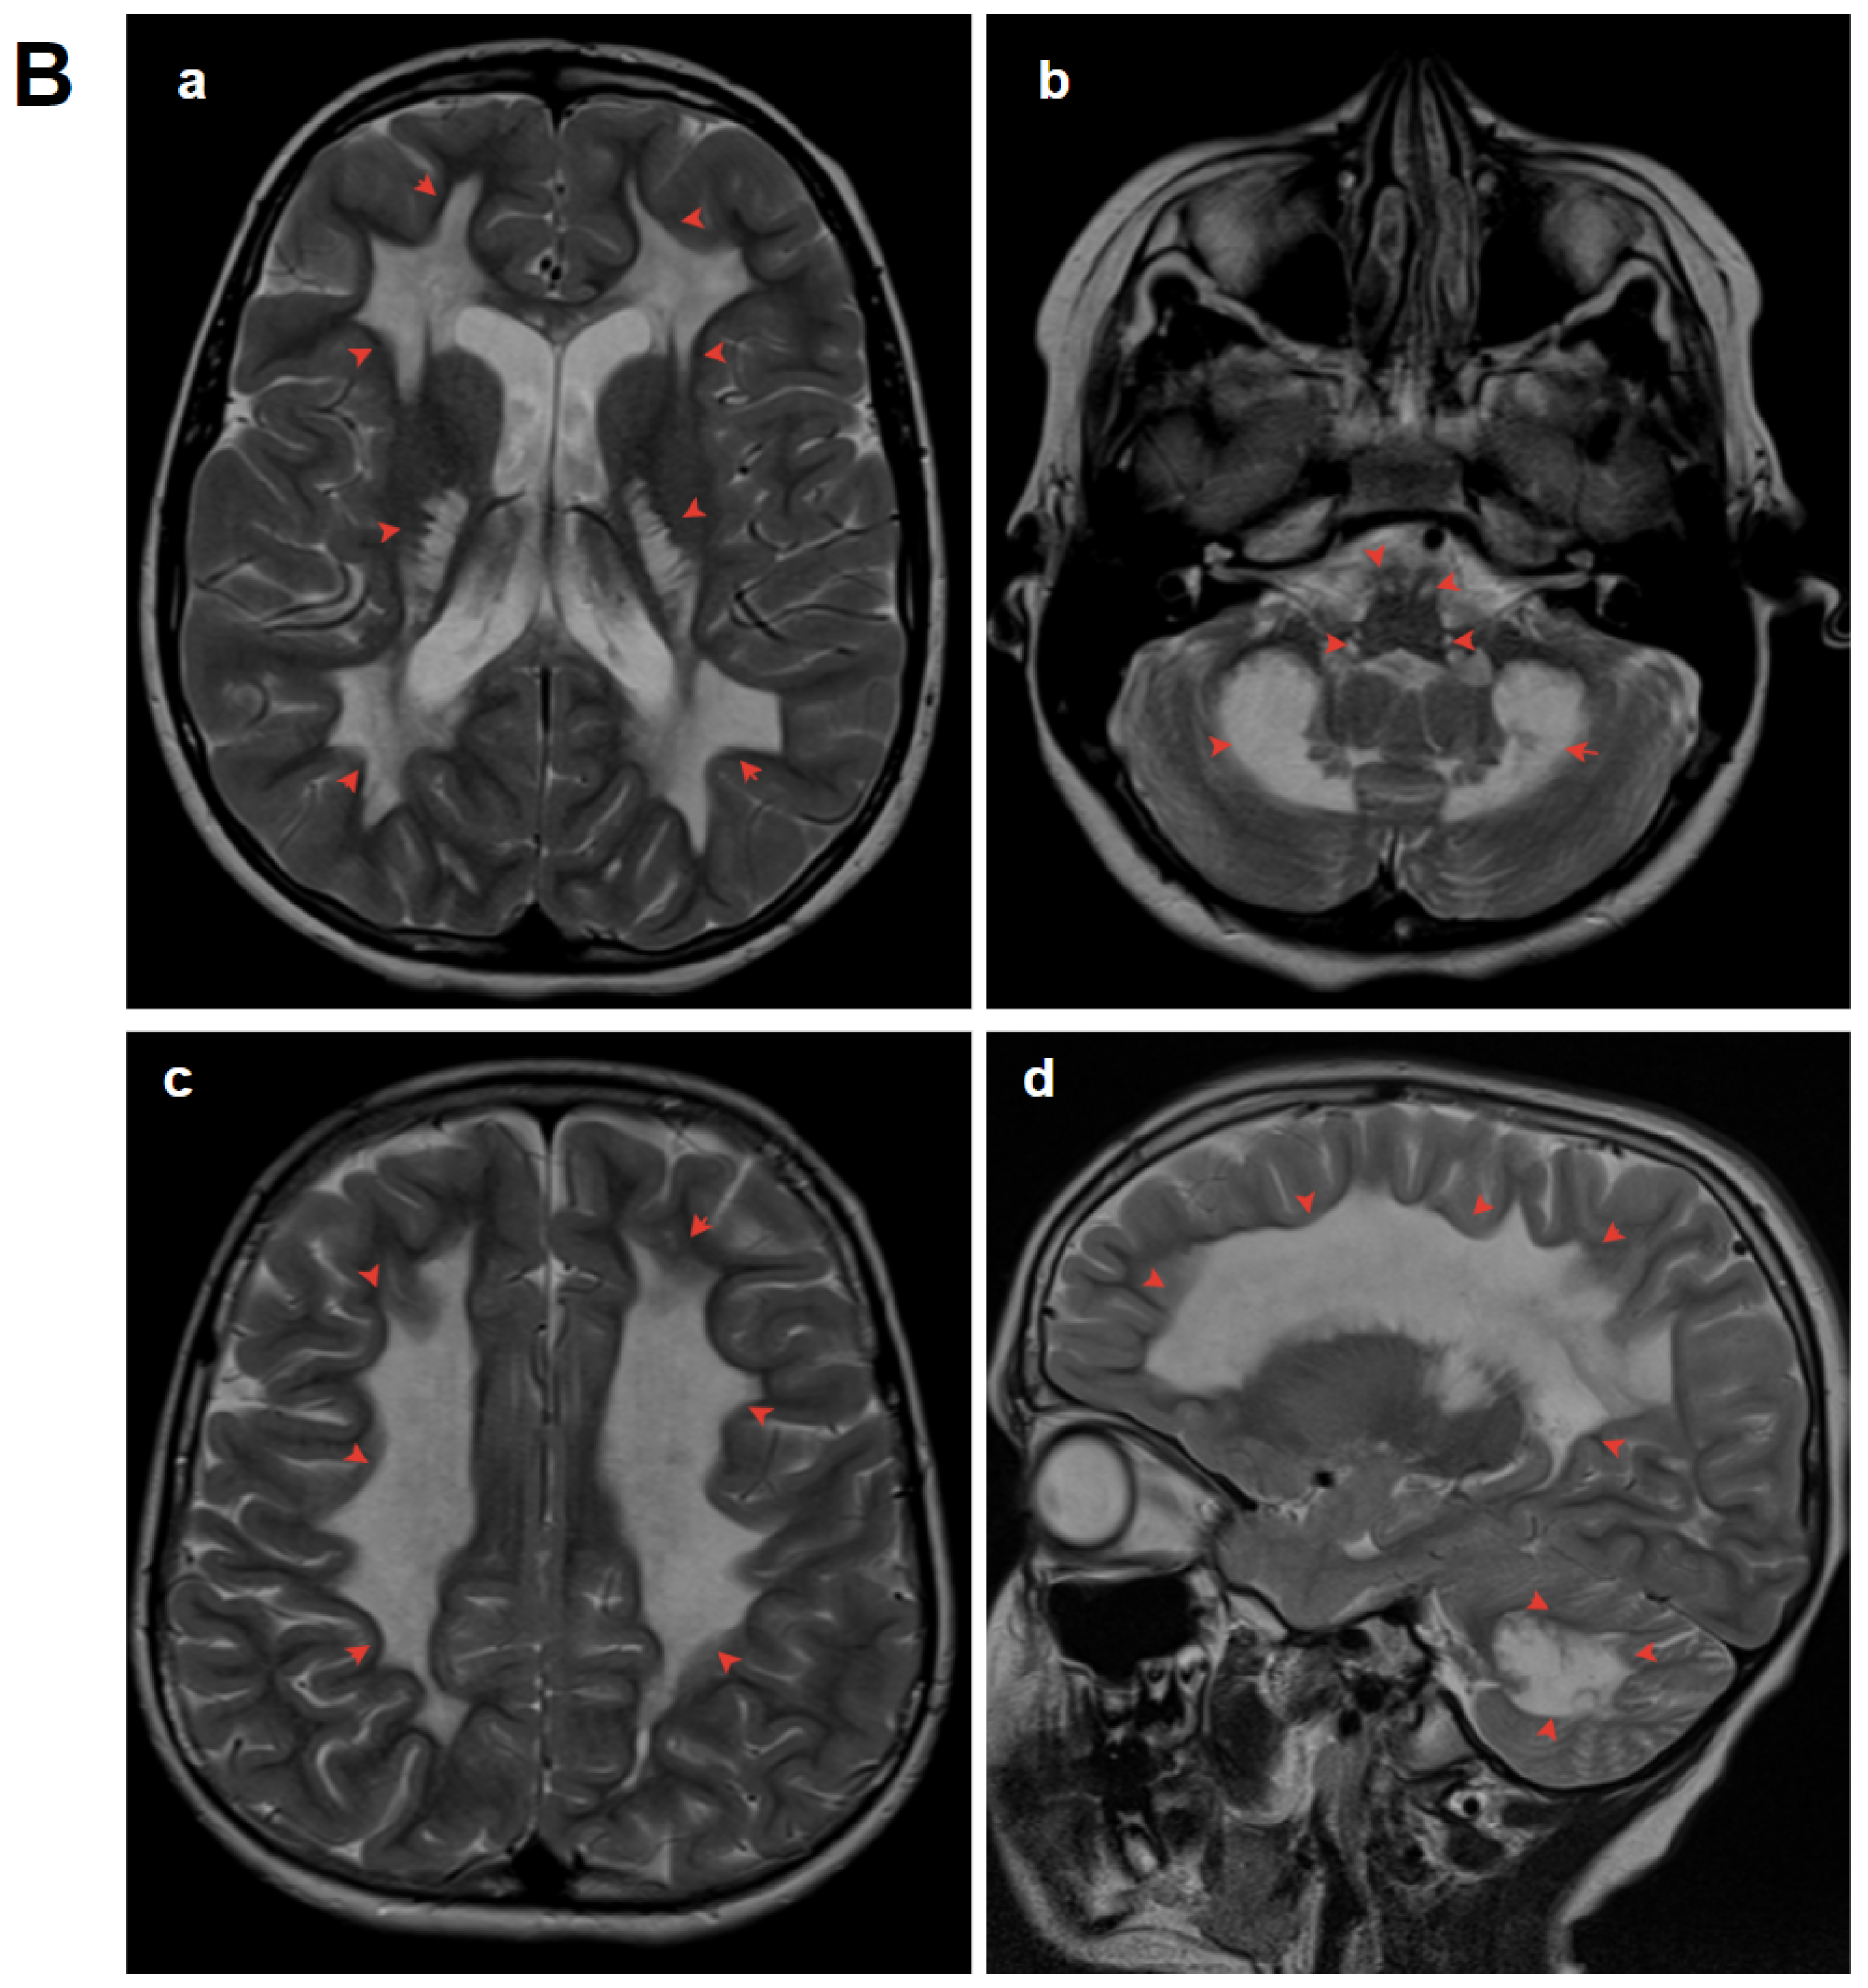

3.1.1. Patient 1